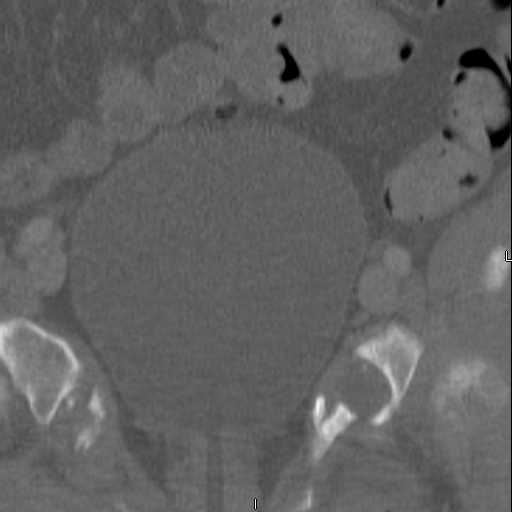

Here are a recent patient’s example slides...

54 yo Female Fell c/o Pain

3 Months After Fall

Continued Pain & Immobility

(+) Instability to Compressive Manual Exam

Pelvic CT Scan - 3 Months After Fall

Sacral Injuries

Ramus Fractures